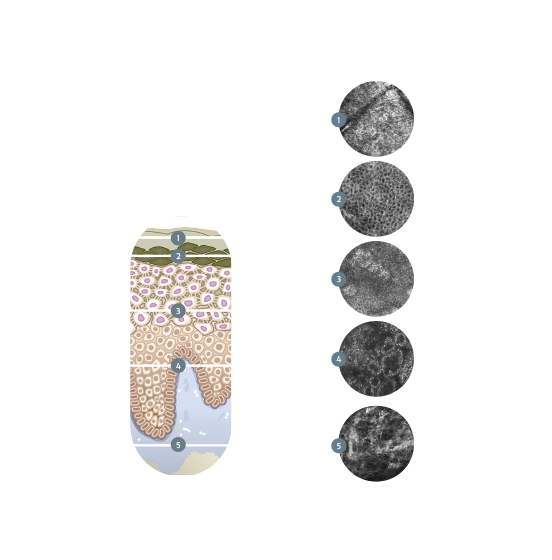

The VivaScope technology (in vivo) allows for a real-time and non-invasive Instant Optical Biopsy from the epidermis to the upper dermis. With the VivaScope confocal laser scanning microscopy (CLSM) the cell morphology of the skin layers are displayed in high resolution.

In vivo examinations with the VivaScope technology using confocal laser scanning microscopy (CLSM) allow for an optical biopsy using a non-invasive procedure. Cellular microstructures of skin can thereby be depicted cell by cell in clearly defined horizontal “optical cross-sections” with a thickness of less than 5.0 μm.

Layer by layer.

In Vivo examinations using confocal laser scanning microscopy (CLSM) allow for an optical biopsy and noninvasive procedure. Cellular microstructures of skin

can thereby be depicted cell by cell in clearly defined horizontal “optical cross-sections” with a thickness of less than 5.0 μm.